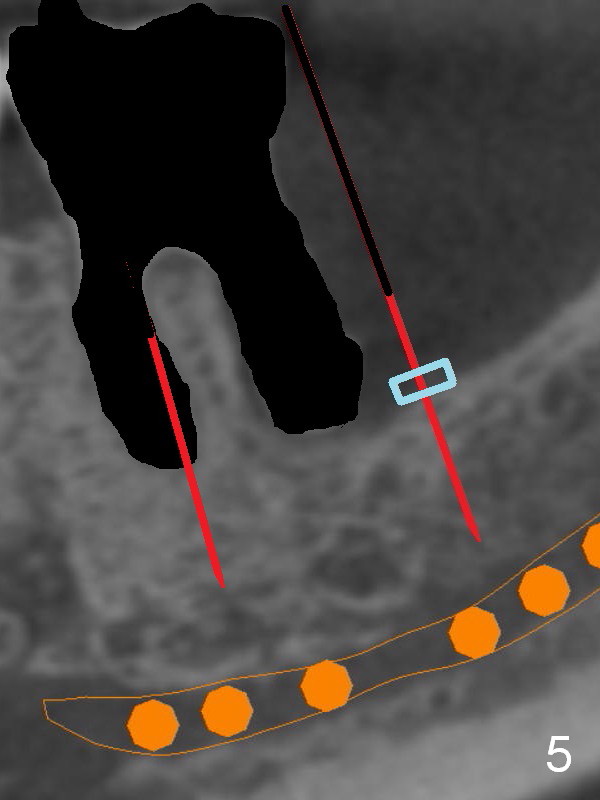

There is severe bone resorption around the distal root of the lower left 1st molar of the 56-year-old man (WG), while the loss of the 2nd molar is associated with limited bone height (Fig.1). A 5x14 mm implant will be placed at the mesial socket of #19 and 5.9 or 6.4x6 mm one is at the mesial site of #18 (Fig.7-9). Use a 2 mm pilot drill with 6 mm stopper from Sinus Master Kit (with extension) to initiate osteotomy at #18 immediately distal to the crown of #19, parallel to the long axis of the latter (Fig.2). After inserting a parallel pin at #18, extract the tooth #19 (Fig.3, antibiotic pending) and start osteotomy with a 2 mm pilot drill with 14 mm stopper (Fig.4). Insert the calibrated parallel pin at #19 (Fig.5) and measure the distance between the two parallel pins (approximately 10 mm, Fig.7). Sequential osteotomy and application of the Tatum taps (Fig.6 red rectangle) will push the septum distal (green arrow). As to #18 osteotomy, trephine, final and tap drills are to be used with control of the depth: 6 mm (Fig.7,9).